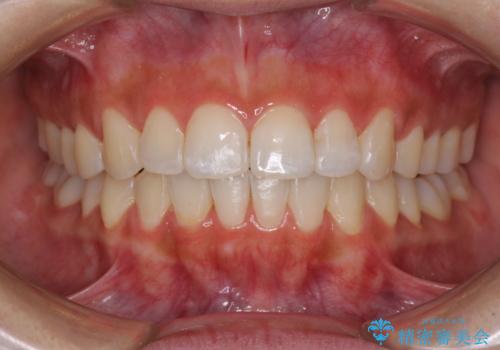

また、下顎前歯の叢生も気になっているとのことで、上顎の治療と並行して部分矯正を行うこととしました。

下顎前歯の部分矯正に半年ほどかかってしまい、少し期間は長いものとなりましたが、上下ともに前歯がきれいに整い、患者様には大変満足していただきました。